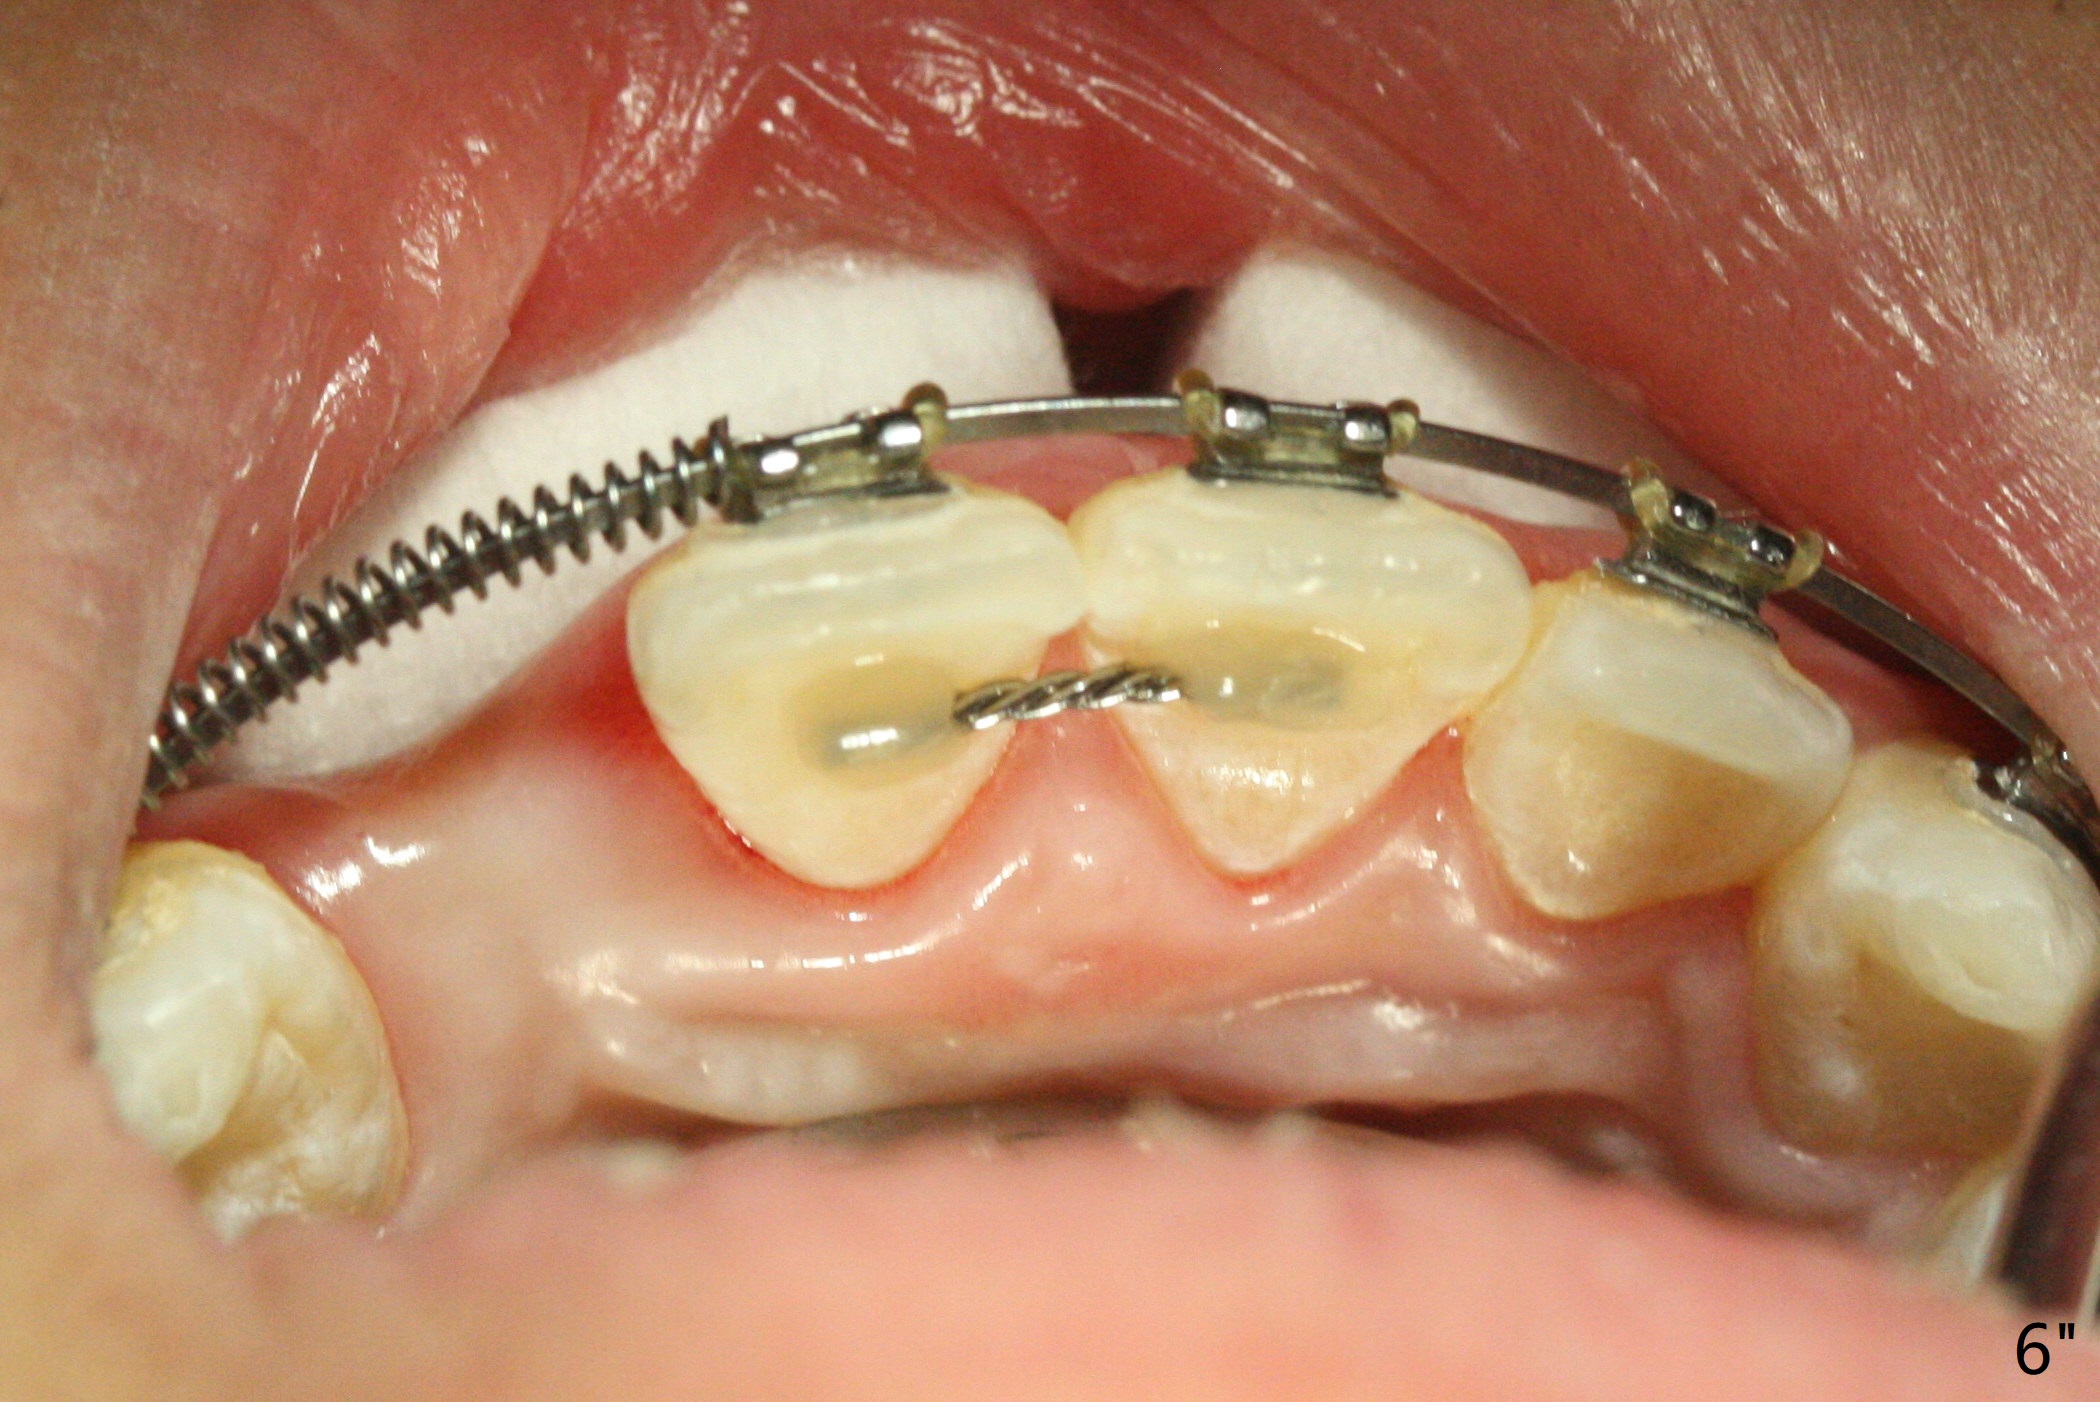

A 15-year-old man finishes orthodontic treatment for congenital missing lateral in 13 months. Molar Class I relationship remains the same (Fig.1,2,4,5). The upper diastemata mesial to 4s (Fig.4,7") close with correction of the upper midline deviation (Fig.2'-4'). The kid is unpleased with the elongated UR1 (Fig.2',3'). In fact it is a preexisting condition (Fig.2 arrow, 2"), but bracket placement at UR1 should have been overcorrected (incisal placement, Fig.3"). The intrusion should be done (Fig.4") before closure of the diastemata, since anchorage may be weakened when the separation between UR1 and 3 increases by using open coil spring. To prevent immediate relapse of the diastema between the upper central incisors, a fixed retainer is placed lingual before debracketing (Fig.6,6',6").